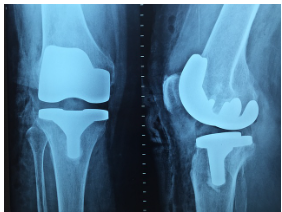

콘드로이친의 가장 잘 알려진 효능 중 하나는 관절 보호입니다. 콘드로이친은 연골의 주요 구성 요소 중 하나로, 연골 조직의 탄력성과 부드러움을 유지하는 데 중요한 역할을 합니다. 연골은 뼈와 뼈가 맞닿는 부위에서 쿠션 역할을 하여 충격을 흡수하고, 관절의 마모를 방지합니다. 나이가 들면서 연골이 손상되거나 마모될 수 있는데, 이때 콘드로이친이 연골을 재생시키고, 손상을 줄여주는 효과를 발휘합니다. 연구에 따르면, 콘드로이친은 퇴행성 관절염 환자들의 통증을 완화하고, 관절의 유연성을 개선하는 데 도움을 줄 수 있다고 합니다.

콘드로이친은 손상된 연골의 재생을 촉진하는 데도 효과적입니다. 연골 손상은 시간이 지나면서 악화될 수 있지만, 콘드로이친은 연골 세포의 성장을 촉진하여 손상된 부위를 복구하는 데 도움을 줍니다. 이는 특히 무릎 관절염이나 고관절염과 같은 질환을 가진 이들에게 중요합니다. 연구에 따르면, 콘드로이친을 섭취하면 연골 조직의 두께가 증가하고, 관절의 기능이 회복될 수 있다고 합니다. 따라서, 콘드로이친은 연골 손상 예방 및 치료에 중요한 역할을 할 수 있습니다.

2019년 연구에 따르면, 6개월 동안 콘드로이친을 복용한 환자들이 플라시보 그룹에 비해 통증이 현저히 감소하고 관절 기능이 향상되었습니다. 이러한 결과는 콘드로이친이 관절염 치료에 효과적일 수 있다고 합니다.

여러 연구에서는 콘드로이친이 연골의 퇴화 과정을 늦추는 데 기여할 수 있음을 보여줍니다. 예를 들어, 2년간 진행된 임상 시험에서 콘드로이친을 장기적으로 복용한 그룹은 연골 손상이 더디게 진행되는 것이 확인되었습니다.